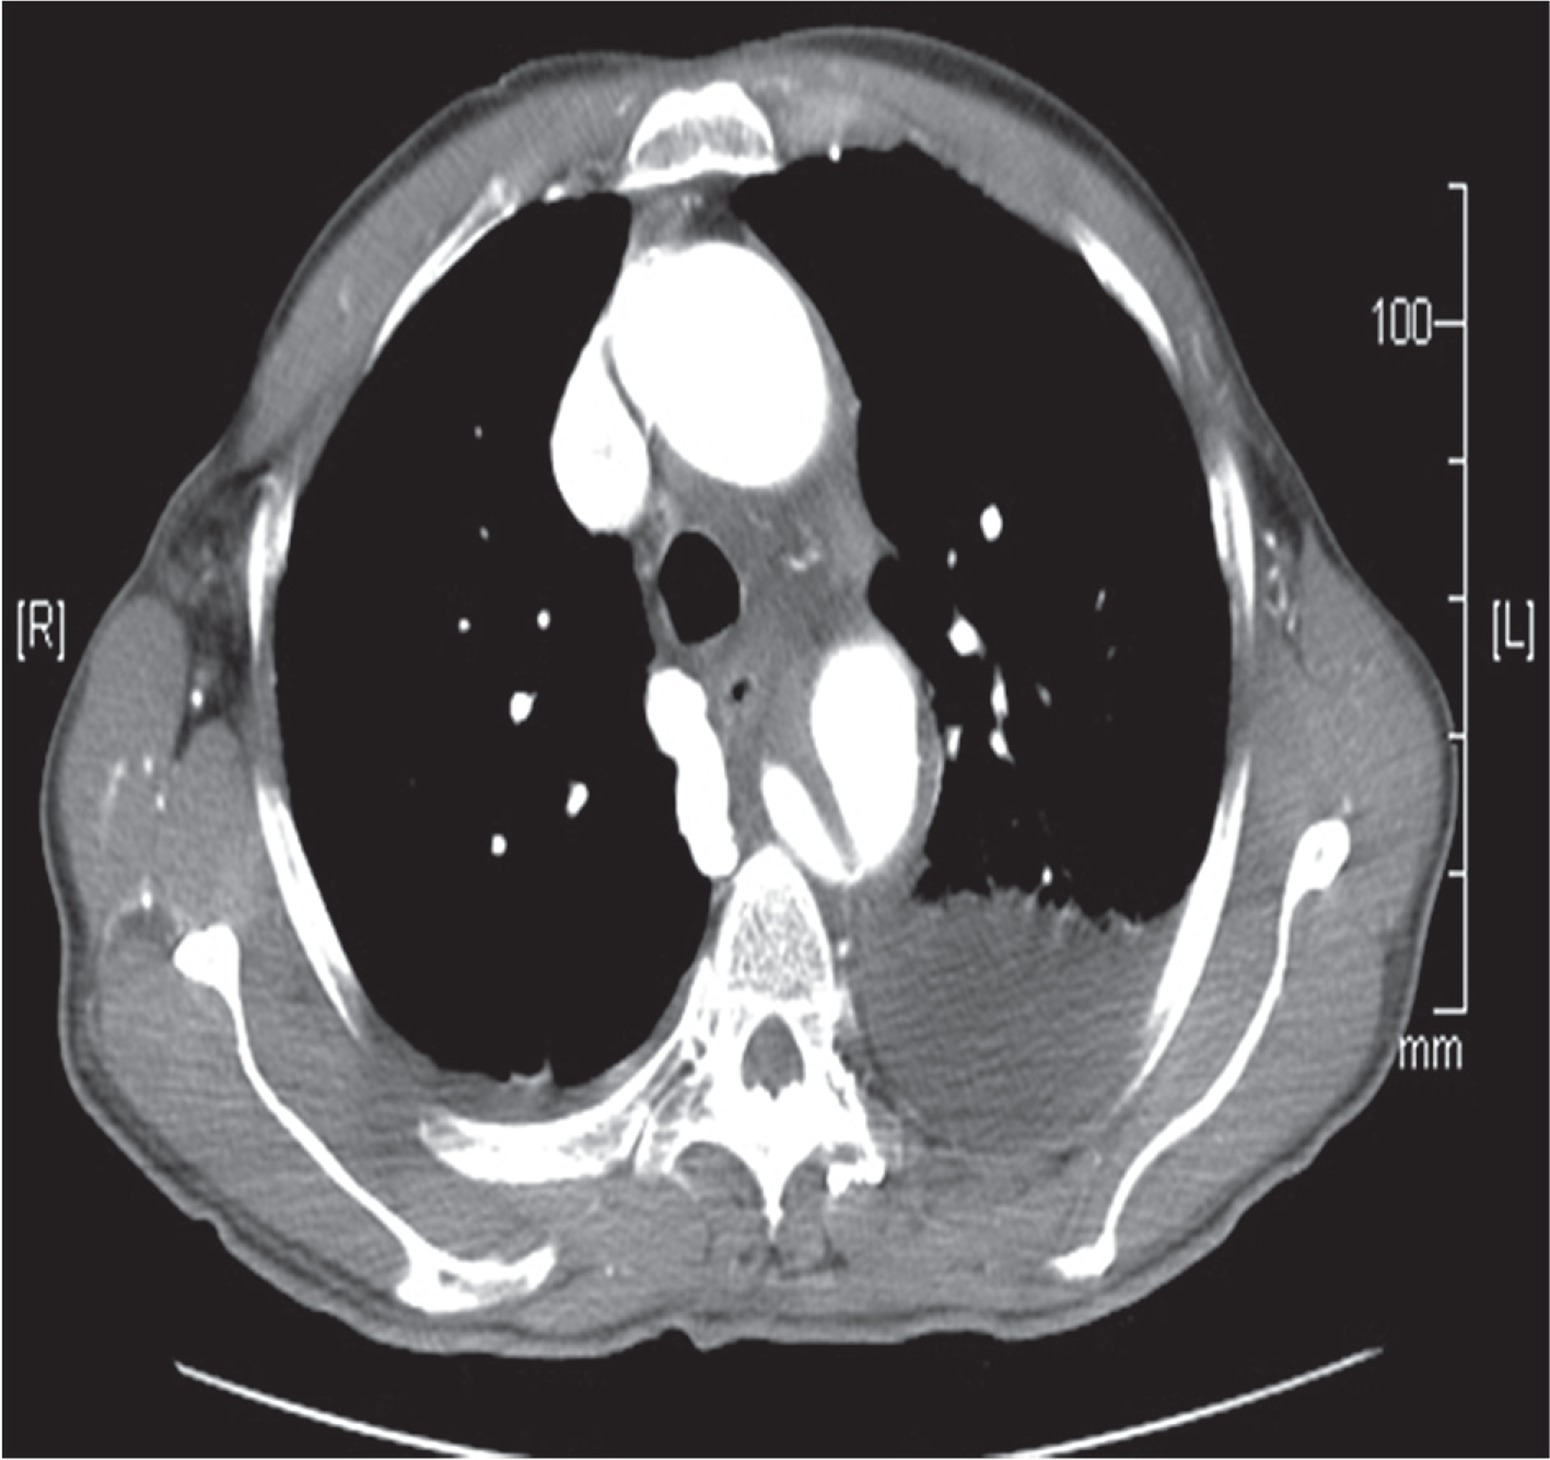

The carotico-carotid bypass preceded the endovascular stent placement. End-to-side 8 mm PTFE grafts were anastomosed to the right and left carotid artery using 6-0 prolene suture with partial cross clamp. Neurological status was monitored throughout the procedure with the Symantec monitoring system. Following the completion of the carotico-carotid bypass the left subclavian artery was coiled with 1 × 20 mm × 8 cm and 2 × 14 mm × 8 cm Nestor coils to prevent future leaks. A Cook Zenith TX -2 thoracic endograft (36/20-2 mm) was implanted in the descending thoracic aorta with the proximal landing zone extending to the origin of the left subclavian artery. Procedural CT angio showed a satisfactory position of the endovascular stent and no endoleaks. Also the carotico-carotid bypass was confirmed to be patent (Fig. 2).

Fig. 2

Computed tomography angiogram confirming absence of endoleak and patent carotico-carotid bypass